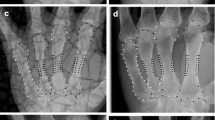

The bone age and the T, W and L measurements for this study (Fig. 2) were automatically calculated by BoneXpert®, a commercially available radiograph analysis software package (Visiana, Holte, Denmark). The hardware and radiograph quality requirements of the software, its method of image processing, and the system’s compatibility with present-day clinical environments have previously been described [40]. The bone age-rating function has been validated in healthy and clinically relevant populations [38, 39, 41–44], and the method of determining T, W and L has been described elsewhere [40].